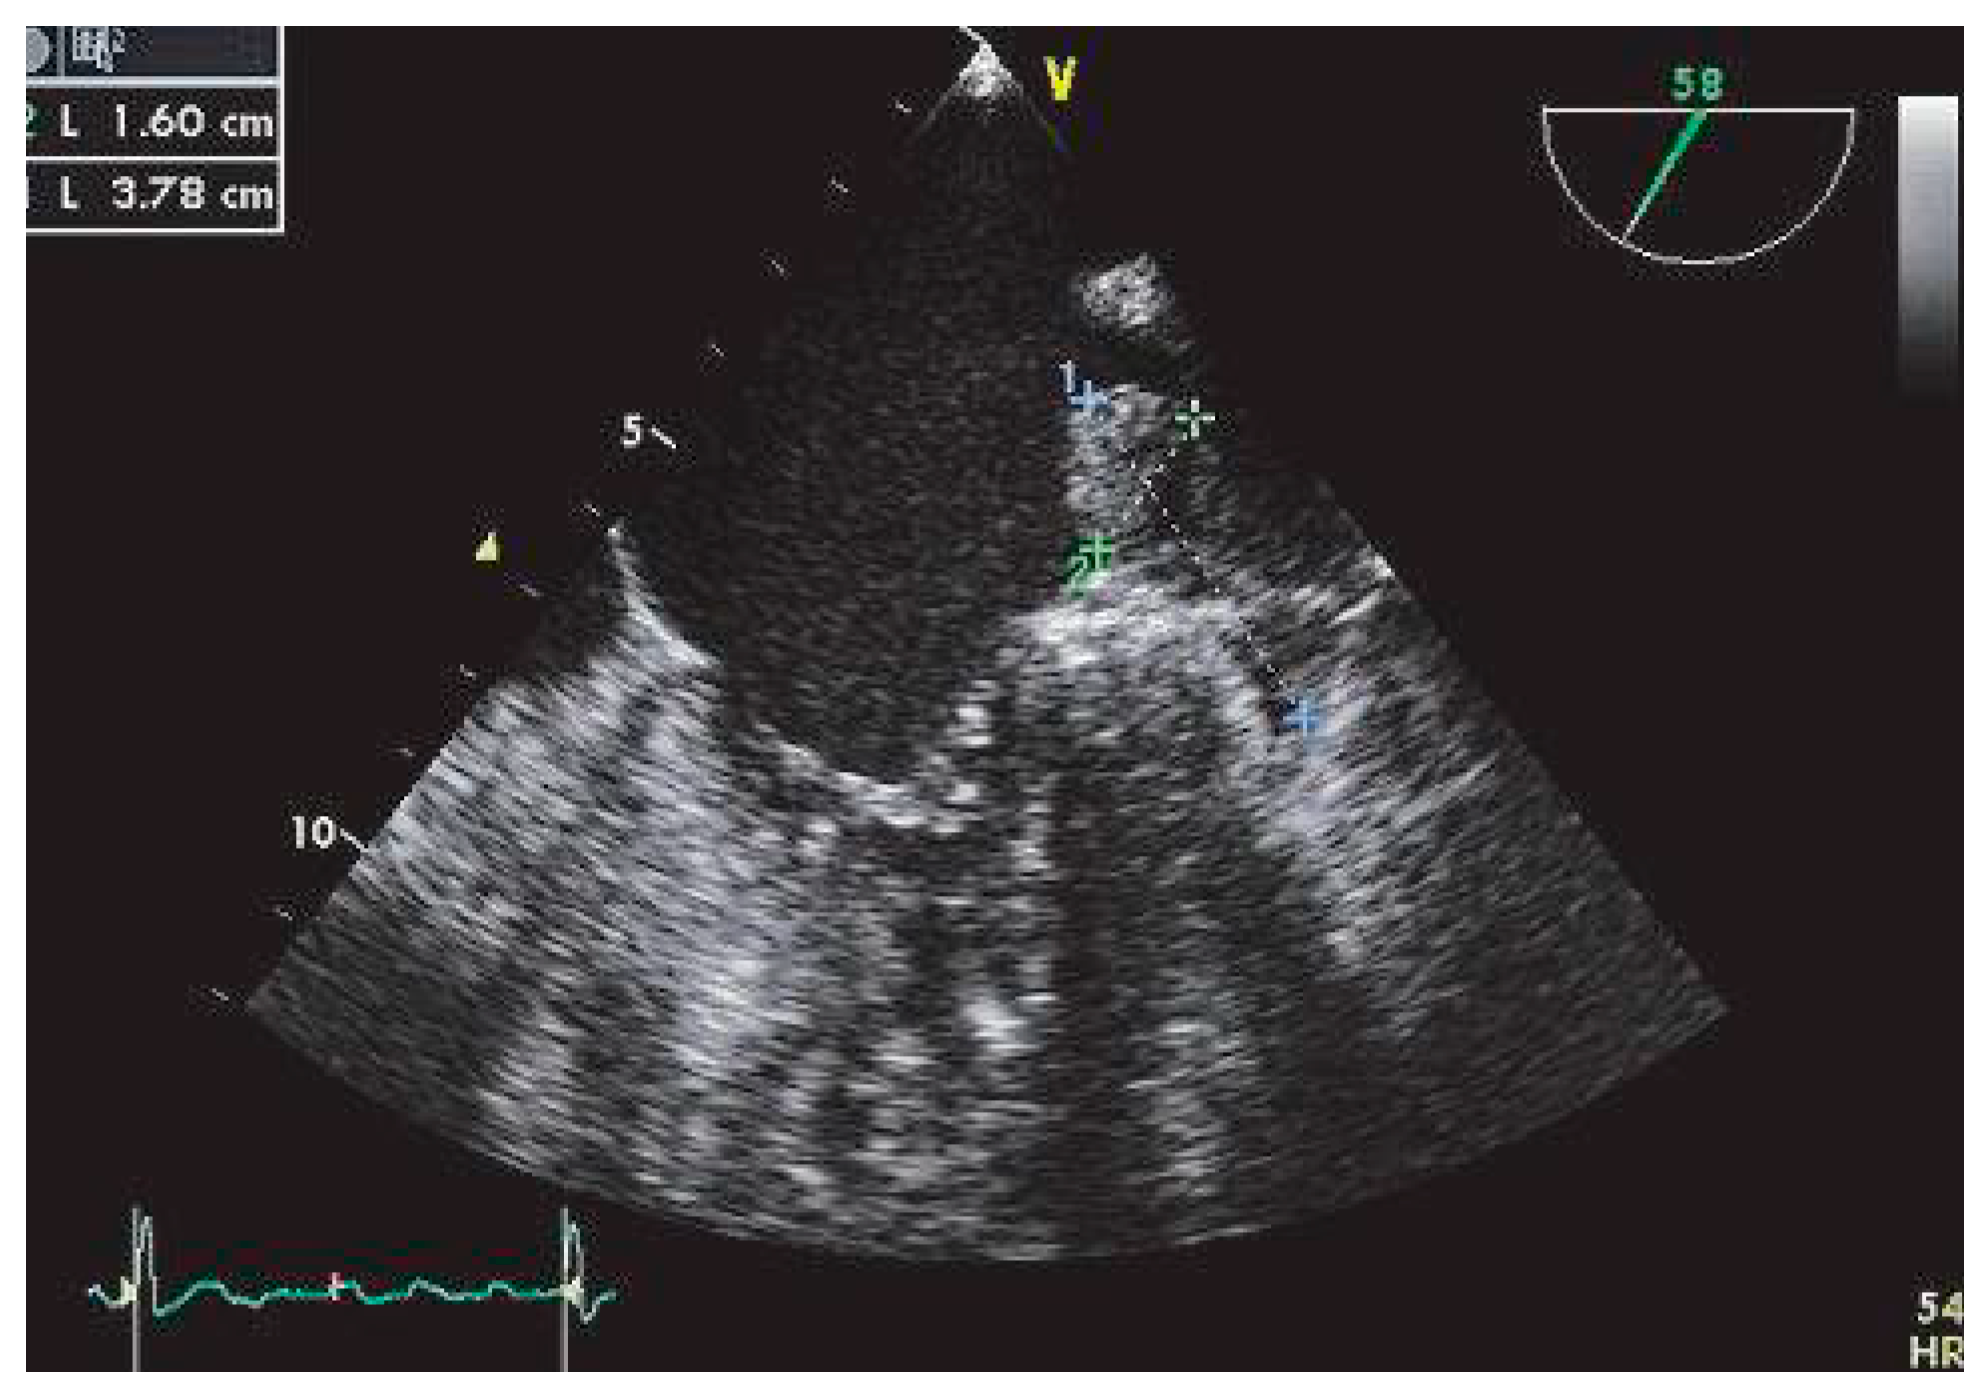

L’analyse des ulcérations de paroi [37,40], des calcifications [41], des thrombi surajoutés et/ou des plaques hypo-échogènes (Figure 4 et Figure 5) permet de mieux identifier les lésions à risque.

La définition échographique habituellement retenue des ulcérations de paroi est la présence d’un cratère de profondeur et de largeur de 2 millimètres ou plus sur une plaque athéroscléreuse. Les travaux concordent en faveur d’un risque accru d’infarctus cérébral en présence de l’association: épaisseur de plaque d’au moins 4 millimètres et irrégularités et/ou ulcérations de plaque.

Dans l’étude cas-témoin de FAPS [39], bien que les calcifications et irrégularités de surface des plaques étaient indépendamment associées à l’infarctus cérébral, l’épaisseur de plaque restait le facteur morphologique le plus fortement associé au risque d’infarctus cérébral. En combinant l’épaisseur des plaques avec la présence ou l’absence des autres paramètres morphologiques (irrégularité de la surface des plaques et calcifications), les plaques de 4 millimètres et plus d’épaisseur non calcifiées étaient le plus fortement associées au risque d’infarctus cérébral, suggérant qu’il puisse s’agir de plaques instables, à haut risque de rupture et de complications.

Dans cette étude [39], un élément mobile était présent chez 7 des 250 patients consécutifs explorés pour infarctus cérébral. Dans 6 de ces 7 cas, l’infarctus cérébral était cryptogénique. La présence d’éléments thrombotiques multiples multiplie par 6 le risque embolique [42].

Figure 4. Trois thrombi mobiles dans la crosse aortique, visualisés en ETO à 0°.

Figure 5. Volumineuse plaque complexe hypoéchogène de la crosse aortique visualisée en ETO à 0°.